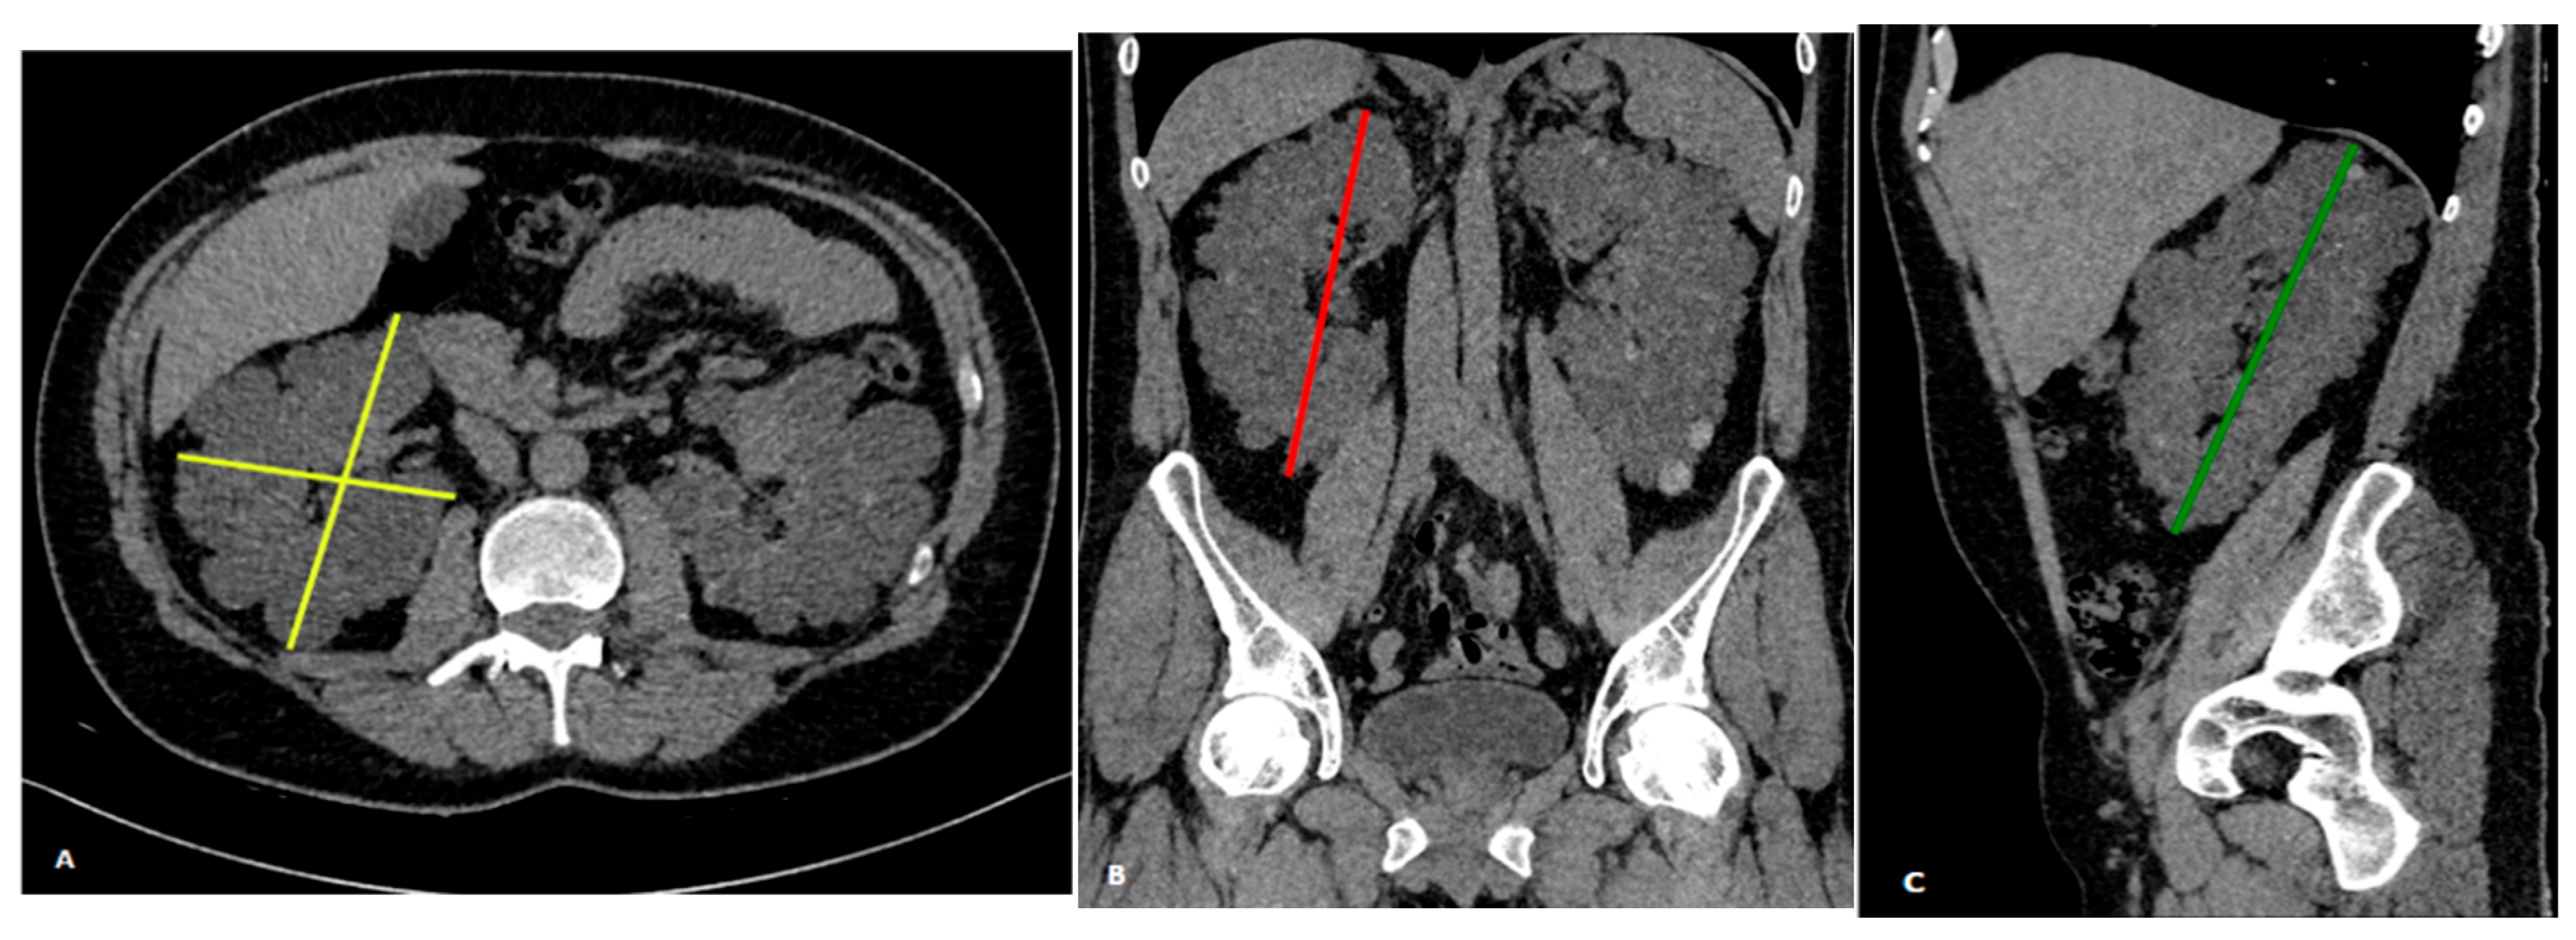

2.4. Ellipsoid Formula